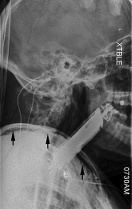

A 35 year-old man with no significant past medical history presented to the emergency department (ED) after abusing phencyclidine (PCP). Responding to command auditory hallucinations, he attempted to swallow his 4 cm × 8 cm smartphone. On arrival, he was agitated but alert, handling his secretions poorly and in moderate respiratory distress. An electronic device was clearly protruding from his oropharynx [throat]…

Emergency physicians immediately attempted to remove the device with Magill forceps, but were unsuccessful. A “trauma code” was announced bringing a surgical intensivist, an anesthesiologist, and appropriate nursing staff to the bedside, while simultaneously indicating that an operating room (OR) should be prepared… The device was successfully removed under procedural sedation without the need for surgical intervention.